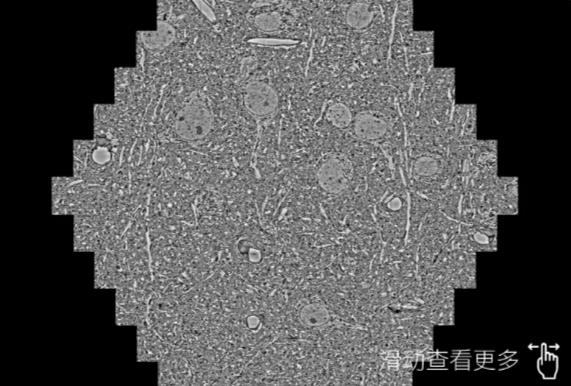

鼠脑切片。左图使用蚌埠蔡司蚌埠扫描电镜MultiSEM706对165μmx143pm面积区域成像,耗时仅需1.5秒。右图为鼠脑切片中30μm区域放大效果。样品由芝加哥大学B.Kasthuri提供。

使用蔡司高速蚌埠扫描电镜MultiSEM对1mm²人脑皮层组织进行高分辨成像,并对其中的各种细胞结构进行三维重构分析。左图展示了2x3mm²组织平面中锥体神经元的三维重构效果。右图显示了局部体积神经元三维重构。图像由哈佛大学chtman实验室提供,渲染图由D. Berger 制作。